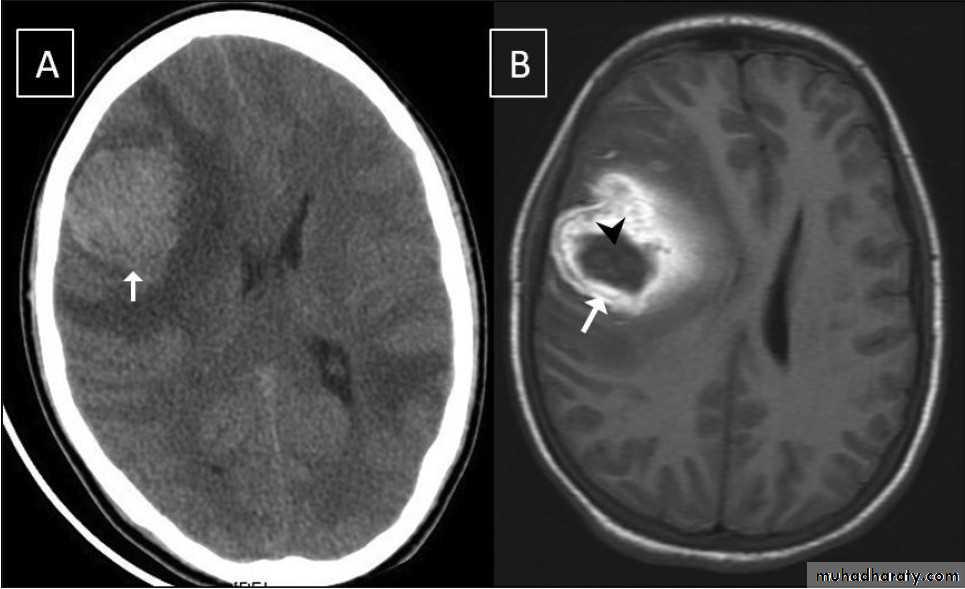

Glioma

Comments primary interracial tumor , vary greatly in malignancy , have many names depending on the histological type :

gliobtastoma multiforme G IV highly malignant t. named also as butterfly G. arise from the anterior or posterior aspect of the corpus callosum , extend & spread to both cerebral hemispheric sides

Low grade G. I well or ill defined lesion iso dence to the brain tissues , not associated with oedeme , no Enhancement , no associated Hemorrhage , necrosis .

From G II , III, various previous finding

IV( glioblastoma multiforme ) are highly malignant have all previous mentioned features .